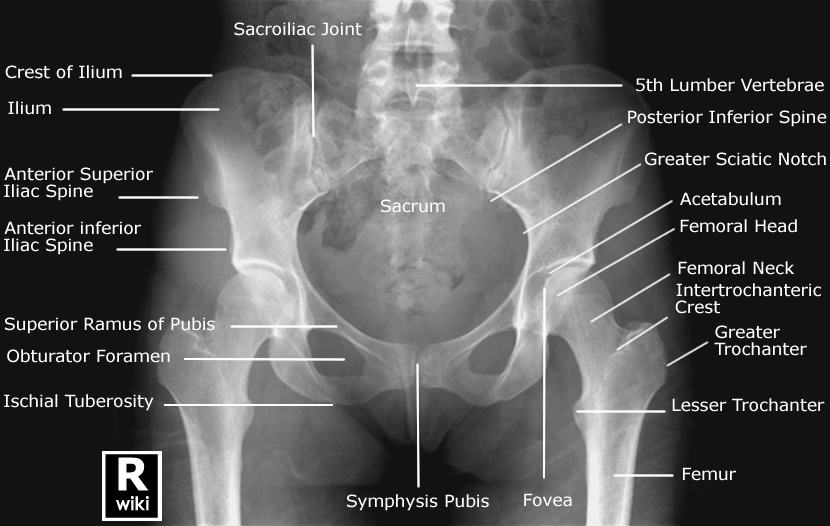

The complete pelvis serves as the base of the trunk and forms the connection between the vertebral column and lower limbs.

What 4 bones does the pelvis consist of?

2 hip bones (innominate bones)

1 sacrum

1 coccyx

What are the 3 divisions of the hip bone?

Ilium: The largest and uppermost part of the hip bone.

Ischium: The lower and back part of the hip bone.

Pubis: The anterior and front part of the hip bone.:

Acetabulum

What is the ilium composed of?

A body ( inferior portion) and an ala (wing)

What is the superior margin of the ala (wing) that extends from the ASIS to the PSIS & is known as the uppermost peak crest?

Crest of the ilium (iliac crest)

What is located below the anterior superior iliac spine (ASIS)?

Anterior inferior iliac spine

What are 2 important positioning landmarks of the ilium?

The iliac crest and the ASIS

What is the most frequently used landmark for the pelvis?

ASIS

Which bony landmark is found on the most inferior aspect of the posterior pelvis?

Ischial tuberosity

What is the name of the joint found between the superior rami of the pubic bones?

Symphysis pubis